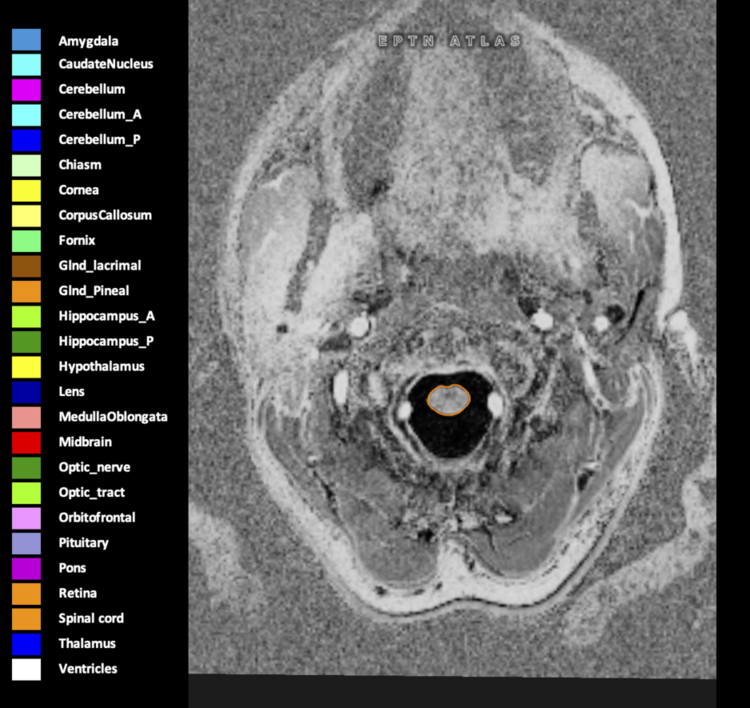

Eekers et al. have published an international neurological atlas for contouring of organs at risk in consensus with the European Particle Therapy Network (EPTN) in 2018 and an update in 2021. The purpose of this consensus atlas is to decrease inter- and intra-observer variability in delineating OARs relevant for neuro-oncology.

Included are all OARs known to be relevant for radiation-induced toxicity in neuro-oncology: brain, brainstem (midbrain, pons, medulla oblongata), chiasm, cerebellum (anterior & posterior), cochlea, cornea, hippocampus (anterior & posterior), hypothalamus, lens, lacrimal gland, optic nerve, pituitary, skin, and vestibular & semicircular canals. To further facilitate research on cognition, vision and radiological changes after irradiation of the brain, potential clinically-relevant OARs are included: amygdala, caudate nucleus, cerebellum (anterior & posterior), corpus callosum, fornix, macula, optic tract, orbitofrontal cortex, periventricular space (PVS), pineal gland, and thalamus.

We propose this atlas is used in photon and particle therapy in order to derive consistent dosimetric data. When required this atlas will be updated according to new insights.

Three-dimensional delineation of the 25 consensus OARs for neuro-oncology are shown on CT (WW/WL 120/40, 3000/600), 3T MR images, (T1Gd, T2FLAIR 1mm) and 7T MR (MP2RAGE 0.7 mm). All are presented in transversal, sagittal and coronal view.